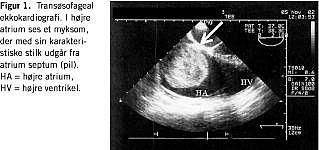

Pga. vedvarende nærsynkoper, svimmelhed, åndenød, hurtig udtrætning ved fysisk aktivitet og natlige tilfælde af hjertebanken blev kvinden 10 mdr. senere via egen læge udredt med transtorakal ekkokardiografi (TTE). Denne viste en 3 × 6 cm stor proces i i højre ventrikel, og patienten blev henvist akut til en specialafdeling. Her blev TTE'en gentaget, nu også transøsofagealt med fund af en stilket proces i højre atrium med stilk til foramen ovale, dilateret højre atrium og grundet periodevis indkiling i triskupidalostiet moderat triskupidalinsufficiens (Figur 1 ). Stetoskopisk fandtes der systolisk mislyd langs venstre sternalrand. Ekg og undersøgelse af biokemi viste normale forhold. Subakut blev der foretaget median sterniotomi med excision af tumor under kardioplegi og ekstrakorporal cirkulation. Der fandtes et 5 × 7 × 8 cm stort myksom med stilk til foramen ovale (Figur 2 ). Efter excision af myksomet fra atrieseptet blev defekten lukket med Goretex patch. Der var et ukompliceret postoperativt forløb. Postoperativ mikroskopi viste myksom med fri resektionsrand. Post-operativ TTE viste normale forhold fraset en diskret triskupidalinsufficiens, og patienten var symptomfri.